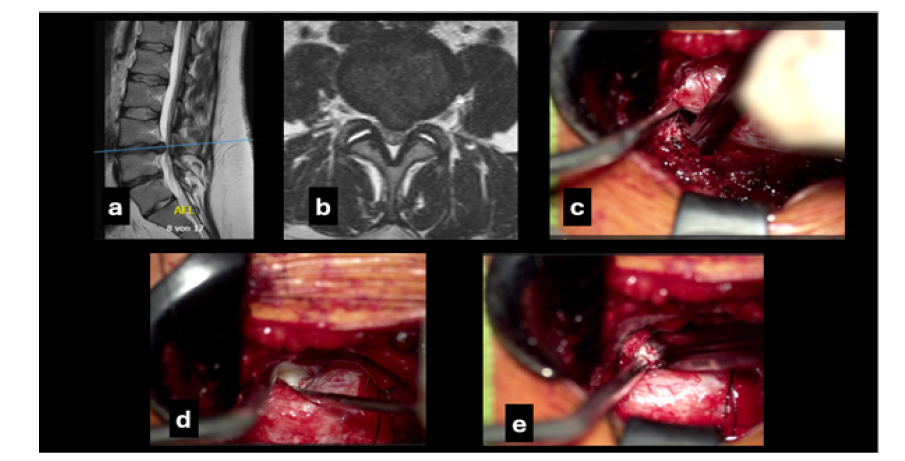

Figure 1:The preoperative T2W magnetic resonance imaging mid sagittal (a) and axial (b) views showing the massive disc herniation. Intraoperative photomicrographs: c: showing ipsilateral disc removal to the surgical approach with a medially angled disc forceps and the aspirator assisting in the retraction of the dural sac; d: after tilting the table about 25 degrees exposure of the contralateral residual disc herniation using a fine, angled nerve hook; c: extraction of the contralateral disc material

A 34-year-old obese female (BMI 33.7) presented emergently with severe immobilizing low back pain (VAS 9) and left anterior thigh and lower leg pain (VAS 7), present for several weeks, with occasional milder contralateral symptoms. ODI was 82. She received ibuprofen 800mg three times daily and tapentadol 50 mg twice daily without relief. Neurological examination revealed left L4 motor deficit (knee extension 3/5), left thigh hypoesthesia and urinary incontinence. MRI demonstrated a massive L4-L5 disc herniation classified as type 2B (AFFM-YOLOv8), with lumbarization of S1. Postoperatively, complete remission of neurological deficits was observed, along with progressive weight reduction. Postrehabilitation ODI was 48. VAS improved to 3 for back pain and 2 for leg pain (Figure 1).